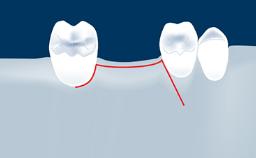

• intraoperative complications of lateral window sinus floor elevation

• intraoperative complications of transcrestal sinus floor elevation